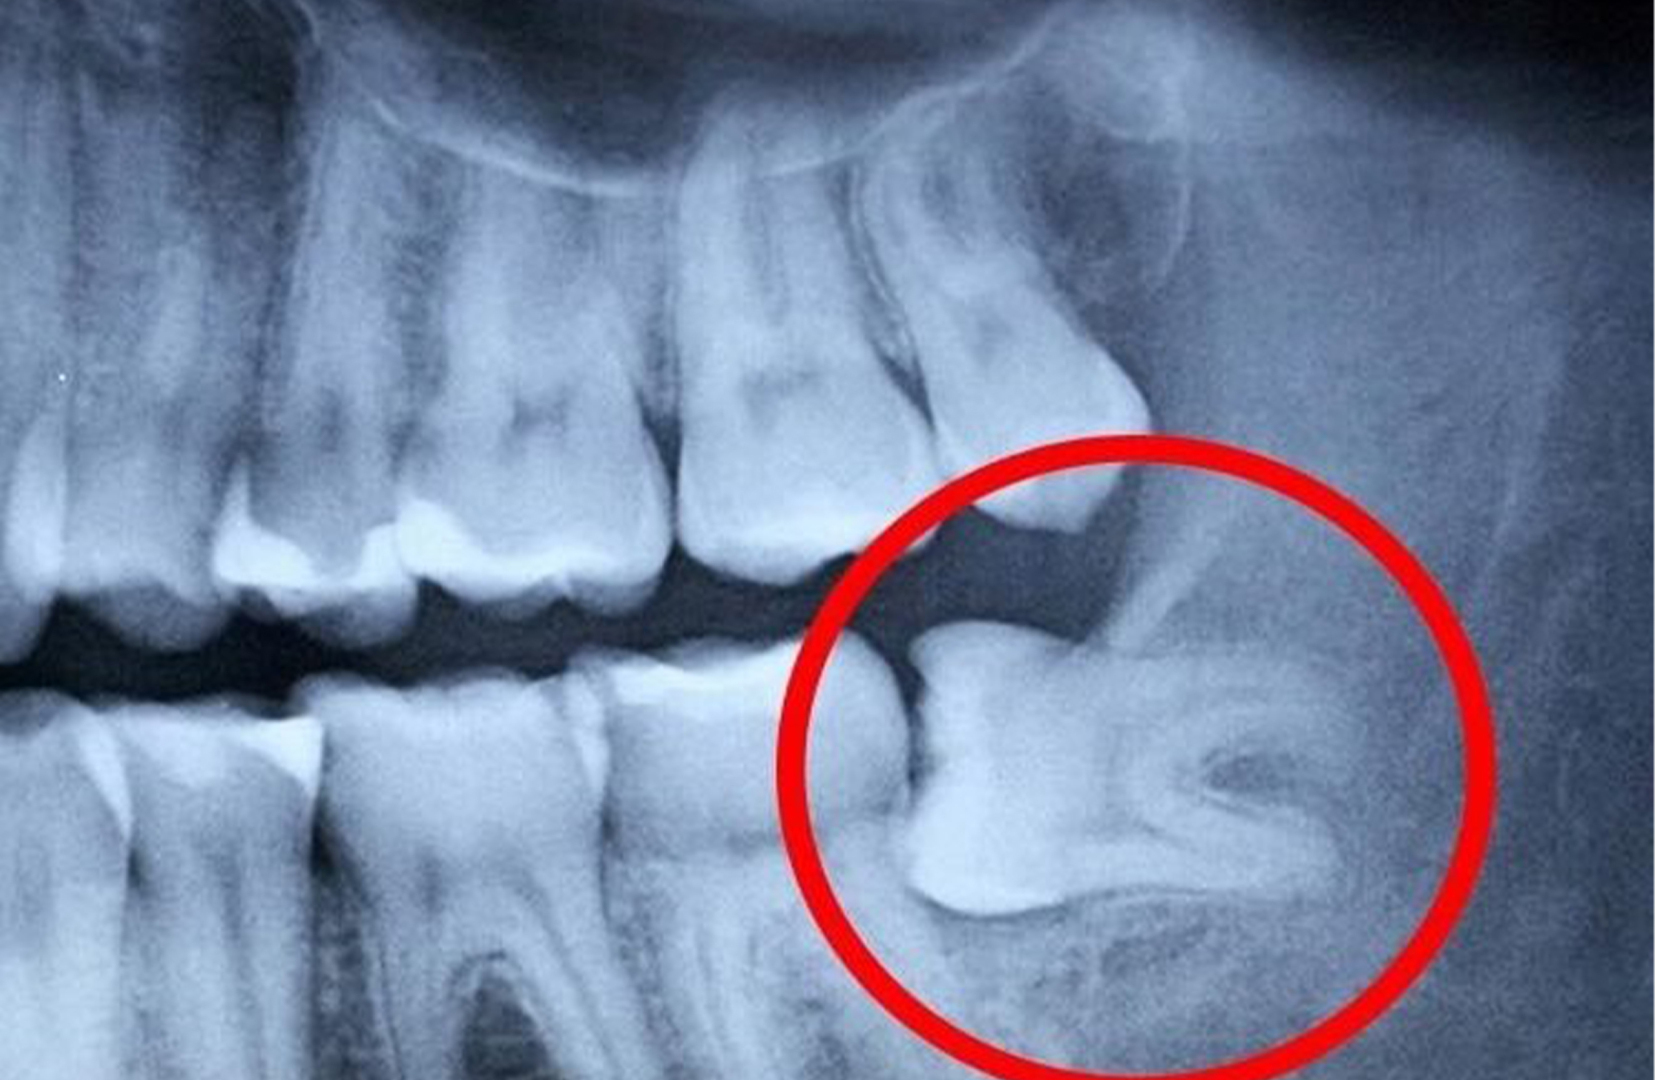

Всякий раз, когда ваши зубы мудрости прорезываются в пространстве, где недостаточно места, велика вероятность, что зуб мудрости станет проблемой. Частично прорезавшиеся зубы мудрости, скорее всего, нуждаются в удалении. Это означает, что зуб наполовину вылез. Он пытается попасть в рот, но блокируется передним зубом или челюстной костью. Ситуация немного патовая. Десны закрывают зуб, задерживая пищу, зуб не может нормально функционировать для жевания, и ему некуда деться. Это наиболее распространенный тип развития зуба мудрости, требующий удаления, поскольку он явно сопряжен со всеми рисками и не приносит никакой пользы.

Часто стоматолог может увидеть, когда зуб приближается к проблемному месту прорезывания, прежде чем он дойдет до этой точки. Это означает, что зуб еще не выдвинулся на поверхность, но он каким-то образом заблокирован. Лучше удалить зуб на ранней стадии, в идеале до того, как у него появится шанс вызвать какие-либо осложнения.

Сейчас не у всех есть пораженные зубы мудрости, и не всем нужно их удалять. Все дело в траектории прорезывания зуба мудрости. Стоматолог, имеющий опыт работы с зубами мудрости, или челюстно-лицевой хирург могут оценить рентгеновский снимок и определить траекторию зубов мудрости.

Горизонтальное направление роста выглядит устрашающе